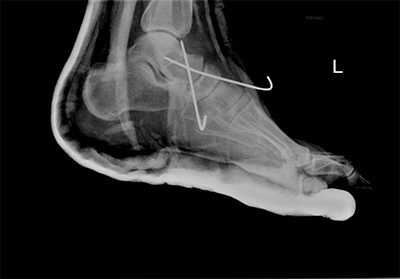

Рис. 8. Переломо-вывих в суставе Шопара

Рис. 9. Переломо-вывих в суставе Шопара

Рис. 10. Чрезкожная фиксация костей предплюсны после вправления вывиха в суставе Шопара, стопа в гипсовой лонгете